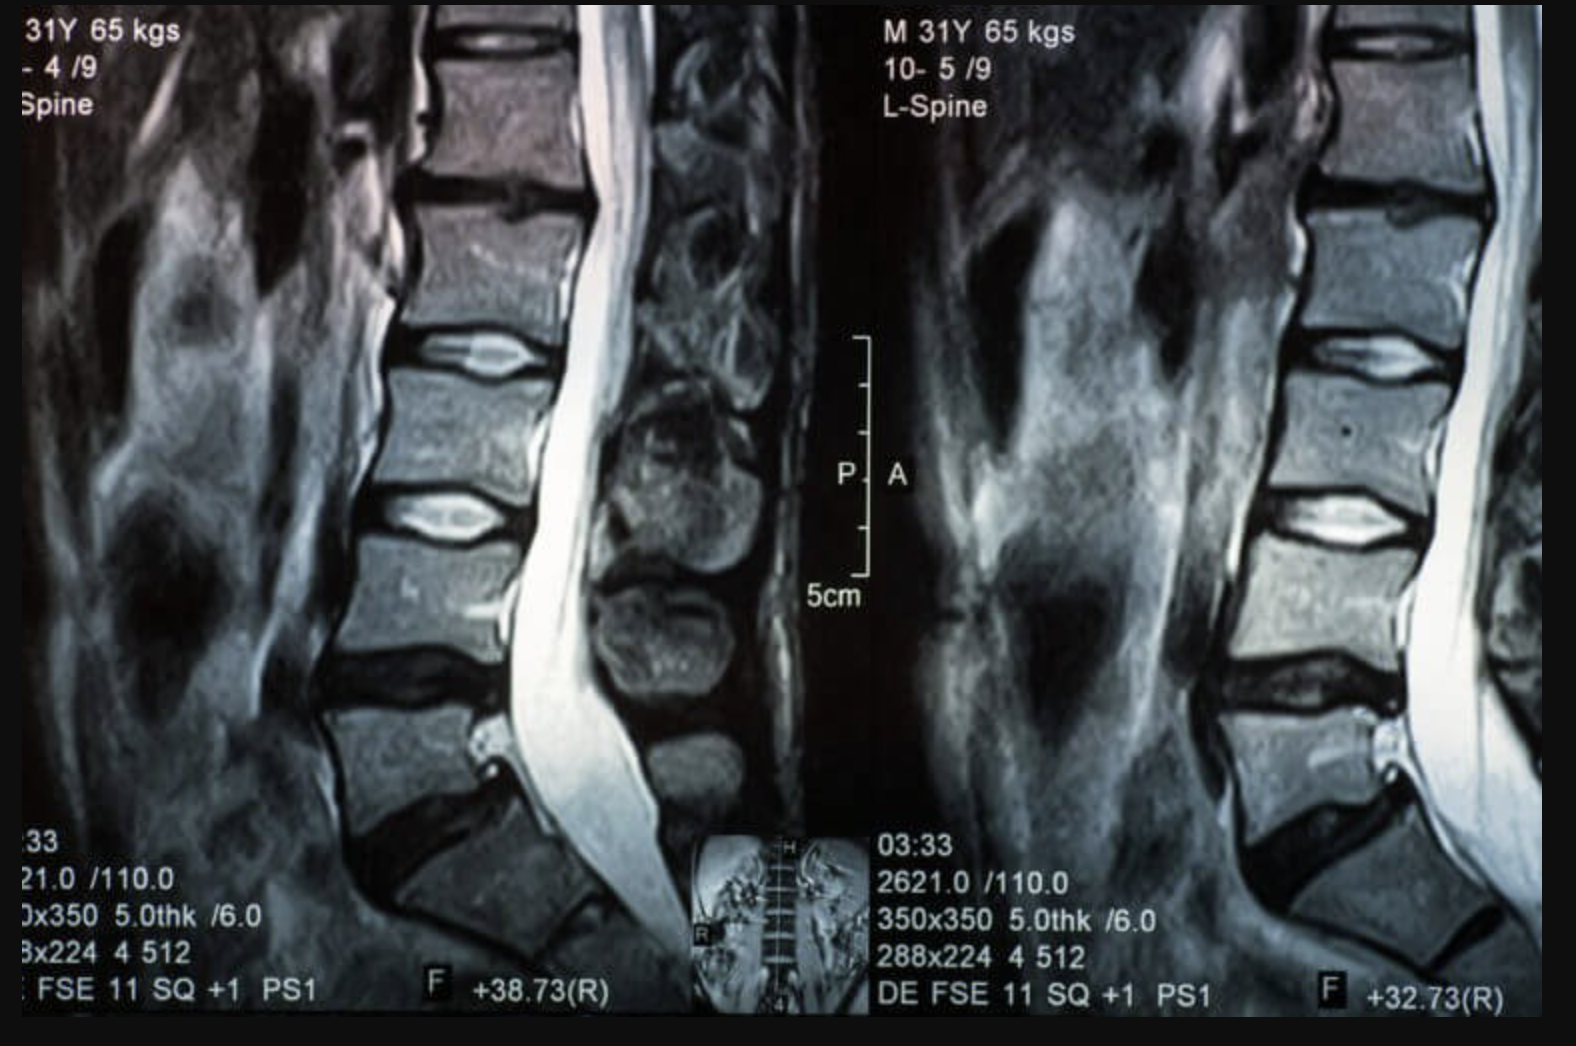

Desde tacones demasiado altos hasta una nutrición deficiente, su espalda puede comenzar a doler por cualquier cantidad de razones. A veces, cuando los discos que absorben los golpes en las vértebras se hernian o se rompen, su centro similar a un gel puede presionar contra los nervios circundantes e irritarlos. ¿El resultado? Puede sentir un dolor significativo. Sin embargo, eso no es una garantía: muchas personas no tienen ningún síntoma. Esto es lo que necesita saber para identificar (o prevenir) con éxito un disco deslizado.

Culpen a los rigores de la vida cotidiana. A medida que envejece, el fluido en estos discos comienza a filtrarse (y deshidratarse) y son propensos a sufrir daños. Hasta un 5% de las personas tendrán esta afección, y es más común en hombres y personas mayores de 30 años. Aquí hay algunas afecciones médicas que afectan a hombres y mujeres de manera diferente.